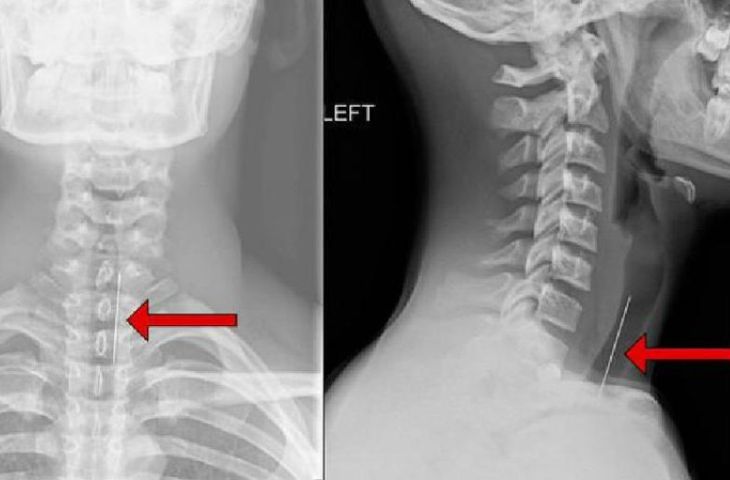

Chụp X-quang cột sống cổ

X-quang là kỹ thuật chẩn đoán hình ảnh phổ biến, thường chụp các tư thế thẳng, nghiêng, chếch ¾ phải, trái. Qua film chụp, bác sĩ có thể phát hiện ra những bất thường của cột sống như: các gai xương, chấn thương xương, mất đường cong sinh lý, lệch đĩa đệm, giảm chiều cao đốt sống đĩa đệm, mất sụn, đặc xương dưới sụn, khối u, hẹp lỗ liên hợp…

điều trị thoái hóa đốt sống cổ Hình ảnh chụp X-quang thoái hóa đốt sống cổ